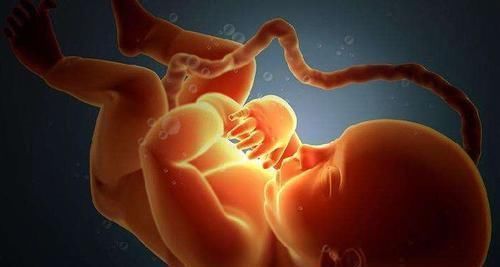

其实宝宝之所以出现脐带绕颈的现象跟宝妈的睡姿没有关系,真正让宝宝脐带绕颈的原因是宝宝自己,随着孩子的生长发育,孩子的身体得到快速增长,所以就比较活跃。

孕妈在羊水充足的情况下,宝宝会调皮的乱动,对于肚子里的宝宝来说妈妈的脐带也是他们的玩具,所以有时候玩着玩着就把自己绕进去了,但是孕妈也不要着急,因为宝宝是可以自己重新绕回来的,别看宝宝小,其实聪明着呢!

虽然有时候医生给宝妈的建议往往是让宝妈调整一下睡姿,但是这并不意味着宝宝的脐带绕颈现象跟宝妈的睡姿有关。调整睡姿一般是为了缓解肚子里宝宝的压力,是为了让宝宝在肚子里舒服一点。

所以妈妈的睡姿跟宝宝的脐带绕颈没有直接联系,而调整睡姿也不能从根本上解决宝宝脐带绕颈的现象。

【 宝妈|胎儿为什么会脐带绕颈多数人以为是受睡姿影响,真相让人意外】一般来说脐带缠绕宝宝脖颈一周或者被脐带搭颈,这对宝宝的压迫程度都是比较轻。所以一般不会发生什么临床症状,也不会对宝宝造成什么伤害,所以孕妈还是可以正常分娩的。

总而言之,脐带绕颈是正常的现象,只要胎儿继续在肚子里活动,那么孕妈就不用那么紧张,但是如果感受到胎动异常,那么为了安全起见,还是去让医生检查一下。